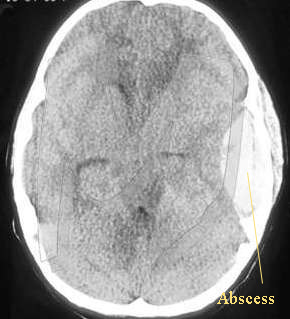

Brain abscess:

Otogenic brain abscess always develop in the temporal lobe or the cerebellum of the same side of the infected ear. Temporal lobe abscess is twice as common as cerebellar abscess. In children nearly 25% of brain abscesses are otogenic in nature, whereas in adults who are more prone to chronic ear infections the percentage rises to 50%. The routes of spread of infection has already been discussed above, the commonest being the direct extension through the eroded tegment plate. Although dura is highly resistant to infection, local pachymeningitis may be followed by thrombophlebitis penetrating the cerebral cortex, sometimes the infection could extent via the Virchow - Robin spaces in to the cerebral white matter. Cerebellar abscess is usually preceded by thrombosis of lateral sinus. Abscess in the cerebellum may involve the lateral lobe of the cerebellum, and it may be adherent to the lateral sinus or to a patch of dura underneath the Trautmann's triangle.

The mortality rate of brain abscess is around 40%, early diagnosis after the advent of CT scan has improved the prognosis of this disease considerably..

Investigations:

CT scan and MRI scans are the present modes of investigation. Scan is ideally performed using contrast media. These scans not only reveal the position and size of the abscess, the presence of localised encephalitis can be distinguished from that of an encapsulated abscess. Associated conditions such as subdural abscess, and lateral sinus thrombosis can also be seen.